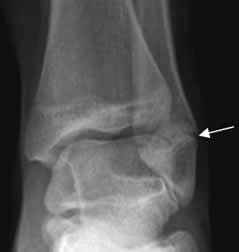

Fig 78 A. Salter tipo V.

A: Rx AP y B: Rx lateral. Disminución del espacio en la placa de crecimiento y esclerosis asociada, en el seguimiento de un deslizamiento epifisiario tipo V.